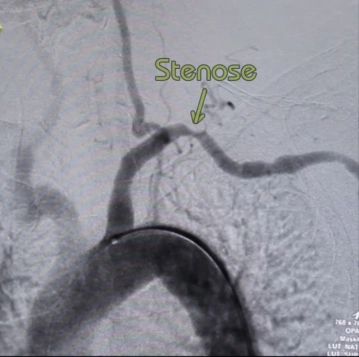

Estenosis o cierre de la A. subclavia solo en caso de sintomatología claramente atribuible / perfusión reducida del brazo:

- Quejas en el brazo similares a la claudicación (isquemia dependiente de la carga)

- Lesiones acrales en el área de los dedos

- Síndrome de robo subclavio